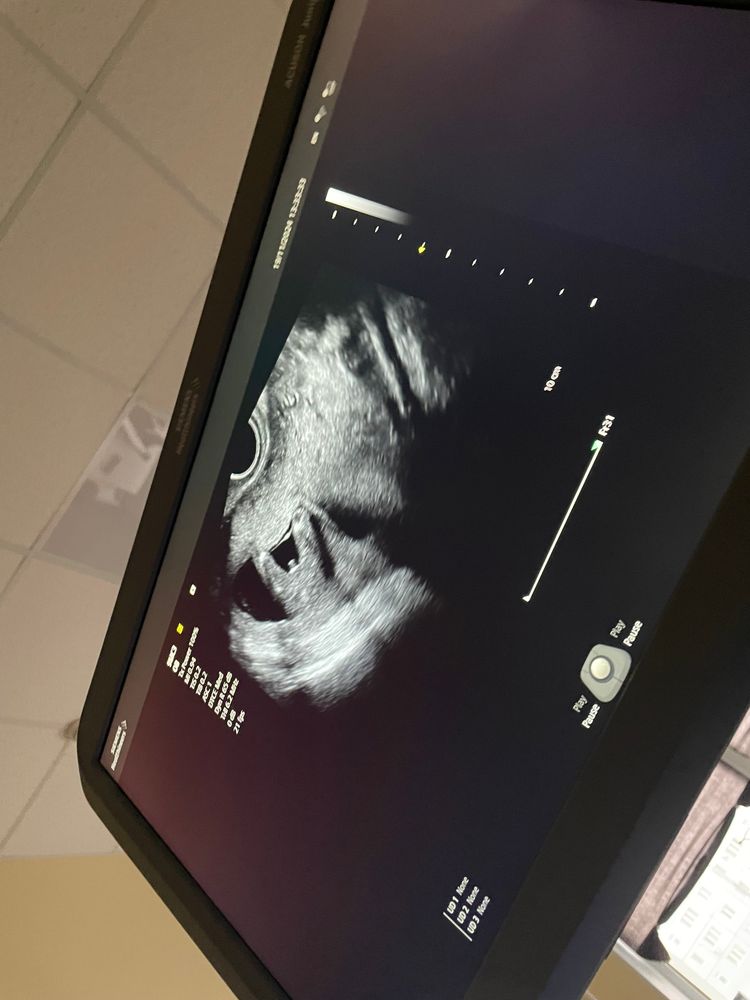

Пол ребенка на 15 неделе

А мне кажется, что девочка (три складки есть), а торчит пуповина...

Виктория , тоже думала про пуповину, а что за складки?)

Мальчик. Поздравляю.)

Ахаха, так четко показал свои причиндалы☺️ мальчишка у вас.

Похоже что мальчик 😄

Это мальчик